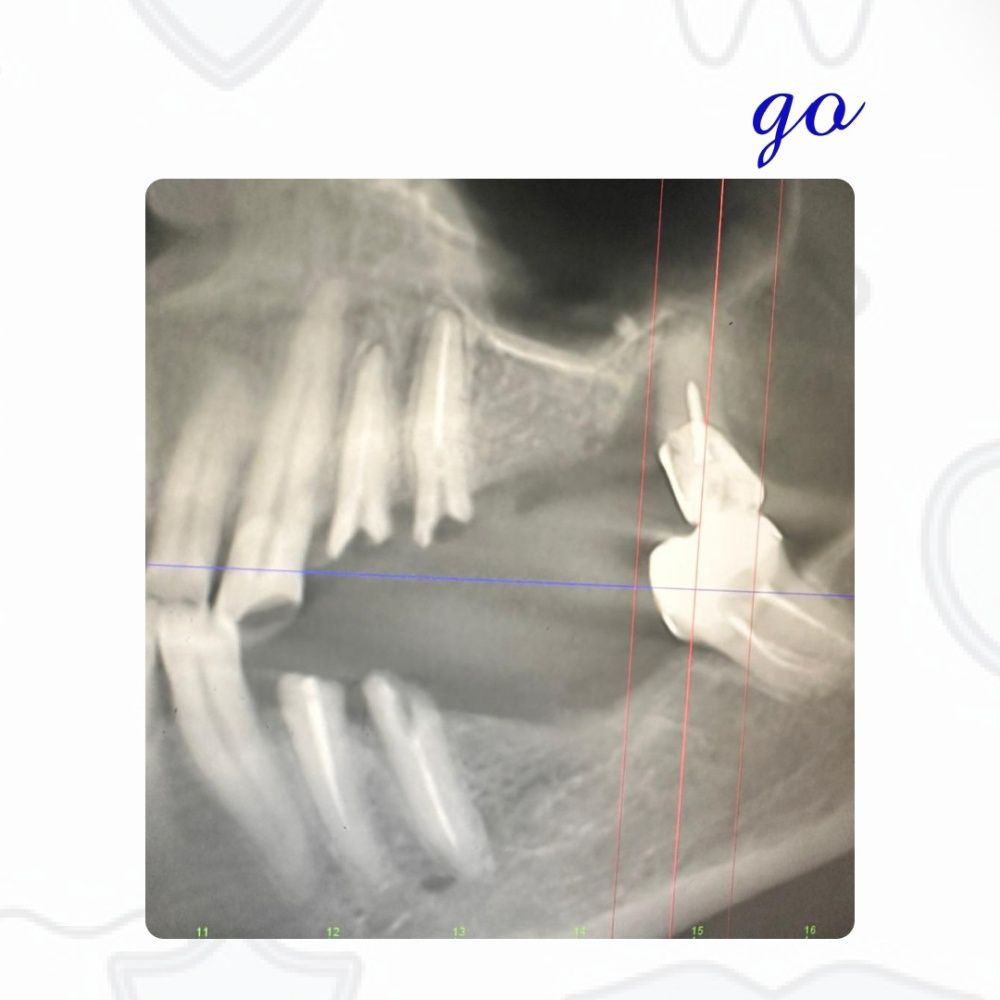

Пациент обращается с жалобой на утрату жевательной функции в области верхней левой стороны челюсти. После тщательной диагностики было принято решение о целесообразности протезирования с использованием дентальных имплантов. В соответствии с ортопедическими показаниями произвели удаление зубов 2.4, 2.5 и 2.8.

В ходе операции были установлены дентальные имплантаты с одновременным наращиванием костной ткани по методу открытого синус-лифтинга. По истечении пяти месяцев пациенту была установлена мостовидная конструкция на дентальных имплантах.